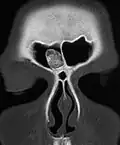

Impressionsbruch der Stirnhöhle in der Computertomographie (Pfeil). Die hintere Stirnhöhlenwand zum Hirnschädel ist hier nicht betroffen. -